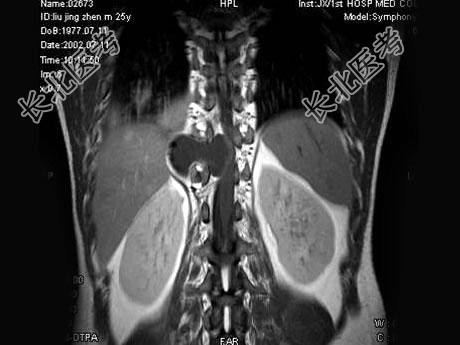

- 单项选择题男,25岁, 慢性腰痛伴间歇性跌倒半年,双下肢无力不能行走1月, MRI见下胸段椎管内肿瘤呈“哑铃”状应诊断为 ( )